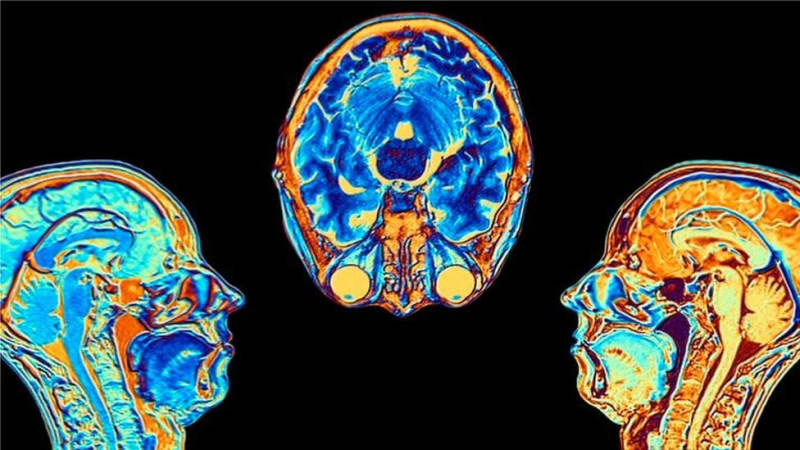

レベッカ・モレル、BBCニュース科学編集長 新型コロナウイルスに感染すると脳に変化が起こる可能性があ…